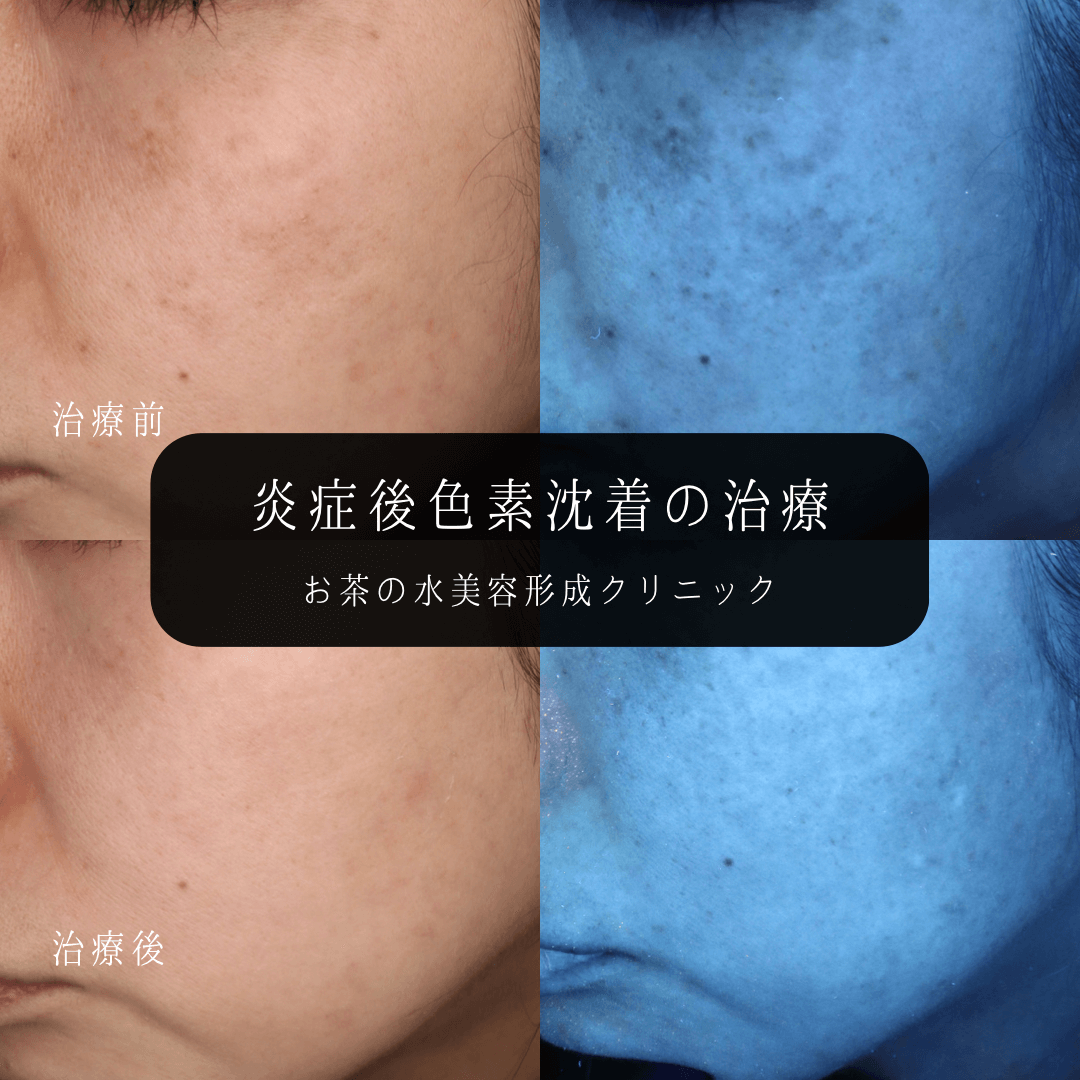

頑固な色素沈着、いつ消える?👨🏻⚕️顔や体にできる色素沈着、時間が経ってもなかなか消えない💦ということはありませんか?今回はさまざまなタイプの色素沈着に有効な治療や おすすめのホームケアをまとめました🙆♂️ 当院での症例も載せています✍️ よく色素。

炎症後色素沈着を治すには?シミやニキビ跡と何が違うの?美容皮膚科の町田マリアクリニック。

炎症後色素沈着とは前田メディカルクリニック栃木県小山市の美容皮膚科。